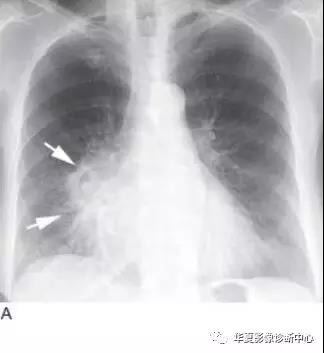

小细胞肺癌常发生在主支气管或叶支气管,造成广泛的支气管周围侵犯,形成肺门增大或肺门旁肿块(图10)。支气管腔内肿块较鳞癌少见,但大的肿块常压迫支气管(图11)引起肺不张。这种肿瘤常伴有显著的纵隔淋巴结增大(图12),是引起上腔静脉阻塞综合征的常见原因。少于5%的病例表现为肺结节。

A.胸片显示右肺门大肿块(箭头);B.CT显示大肿块(M),中叶小叶间隔增厚引起的间质增厚提示肿瘤沿淋巴管播散。